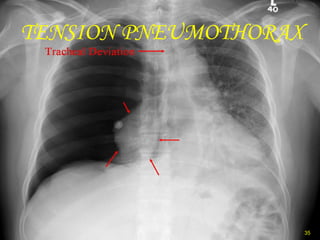

TENSION PNEUMOTHORAX

• #35 Here air has built up under pressure in the pleural space and collapsed the lung severely compromising ventilation. The pressure builds due to a ball valve type leak of air into the pleural space with air going into the space on each inspiration.